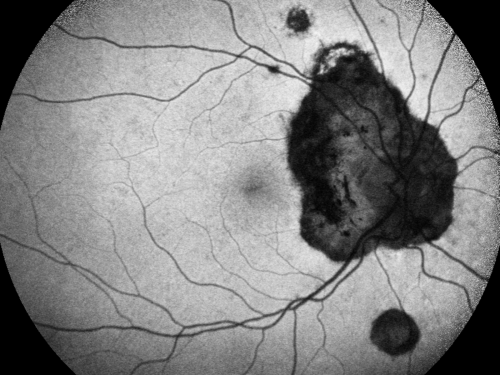

Ocular Histoplasmosis both Eyes - Laser Right Eye Only Fundus Autofluoresence

58-year-old woman who lost vision as a child in the left eye from ocular histoplasmosis.  She used to play in her attic and she was told by her pulmonary doctor that is probably where she picked it up.  She had laser in the right eye for a leaky lesion back in 1990.  OD 20/25,  OS 20/200.